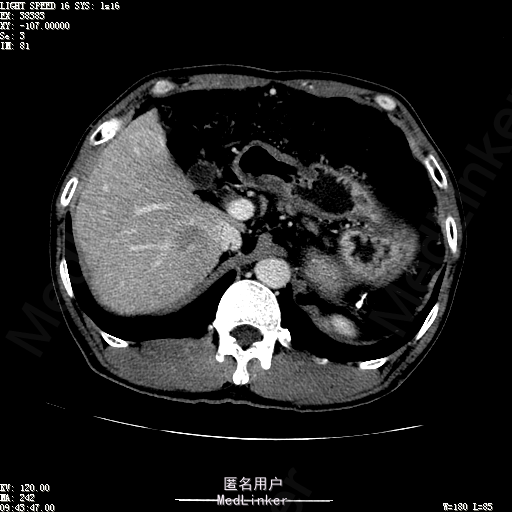

查体:体温36.4℃,脉搏76次/分,呼吸18次/分,血压110/70mmHg。神志清晰,发育正常,营养中等,体位自如,表情安静,慢性病容,检查合作。皮肤粘膜颜色正常,无瘀点、紫癜,有肝掌,无蜘蛛痣,无水肿,毛发的生长与分布正常。浅表淋巴结浅表淋巴结未触及肿大。无巩膜黄染,结膜正常。口唇红润,粘膜正常,舌正常,牙龈正常,扁桃体无肿大,无咽部充血。颈部外形对称,颈静脉正常,肝颈静脉回流征阴性,气管居中。甲状腺正常,无颈部血管杂音。胸部形态正常,呼吸运动平稳规律,无呼吸困难,肋间隙正常。触诊语颤正常,无胸膜摩擦感,肺下界位于右锁骨中线第六肋间。呼吸音正常,未闻及干湿啰音,无胸膜摩擦音。无心前区隆起,心尖搏动正常,心率:76次/分,心律齐,心音正常,无杂音,无心包摩擦音。无大动脉及周围血管征,无奇脉及交替脉,无水冲脉,无枪击音,腹型对称,无腹壁静脉曲张,未见胃肠型及蠕动波,无瘢痕,脐部正常。无压痛,无反跳痛,无腹肌紧张,无腹部包块。肝未触及,Murphy征阴性,脾未触及,肾未触及,无移动性浊音。无肝区叩击痛,无肾区叩击痛,无脾区叩击痛。肠鸣音正常4次/分,无气过水声。外阴及肛门:未查。四肢正常,关节正常,无下肢水肿,无下肢静脉曲张,无杵状指趾。 辅助检查:彩超:肝表面欠光滑,肝内占位5.2*5厘米 ct如下图

诊断:乙肝肝硬化 代偿期 原发性肝癌。 患者病史明确,目前化验转氨酶轻度升高,说明有活动性肝损伤,白蛋白降低提示肝脏合成代谢功能下降,AFP从一年前至今逐渐升高,提示活性肿瘤细胞增多。CT所见明确诊断肝癌,并有周围卫星灶,应近期行TACE治疗。 处置:DSA下肝动脉造影及TACE 手术简要经过:患者平卧位,术区皮肤消毒,铺手术巾,2%利多卡因局麻后,Seldinger法穿刺右股动脉,入血管鞘,5F猪尾管腹主动脉造影,超滑导丝yidao5F RH管腹腔干、肠系膜上动脉、左肾动脉分别造影,腹腔干造影时,见肝右叶7-8处小结节样肿瘤染色,未见外凸生长较大病灶染色。微导管超选肝右动脉注入三氧化二砷碘油混悬液10毫升,横结肠遮挡部位见较大病灶有伞状碘油沉积。复查造影未在见肿瘤染色,拔出导管和血管鞘,穿刺处压迫止血,加压包扎。术毕。

患者术后8天来,无不适,无发热,无腹痛和腹胀,无恶心呕吐,食欲睡眠好,尿便正常。 查体:神志清,巩膜无黄染,心肺听诊无异常,腹软,无压痛,肝脾肋下未触及,移动性浊音阴性,双下肢无浮肿。 复查化验结果:丙氨酸氨基转移酶 116 U/L、天门冬氨酸氨基转移酶 41 U/L、胆碱酯酶 1995 U/L↓、总蛋白 56.3 g/L、白蛋白 25.9 g/L。白细胞计数 5.8 10^9/L、红细胞计数 3.18 10^12/L、血小板计数 175.0 10^9/L、*血红蛋白 83 g/L、血小板分布宽度 15.7 、血小板压积 0.175 %、*红细胞压积 24.6 %、平均红细胞血红蛋白 26.1 pg、平均红细胞血红蛋白浓度 337.0 g/L、平均红细胞体积 77.5 fL、平均血小板体积 10.0 fL、嗜碱性粒细胞百分比 0.4 %、嗜碱性粒细胞数量 0.02 10^9/L、中性粒细胞百分比 70.4 %、中性粒细胞数量 4.10 10^9/L、嗜酸性粒细百分比 2.1 %、嗜酸性粒细胞数量 0.12 10^9/L、单核细胞百分比 12.2 %、单核细胞计数 0.7 10^9/L、淋巴细胞数量百分比 14.9 %、淋巴细胞计数 0.9 10^9/L。甲胎蛋白 23564.00 ng/mL 患者术后第8天开始行FOLFOX6化疗。CT上可见明显碘油沉积,术后甲胎蛋白下降治疗有效。嘱患者术后必须定期复查